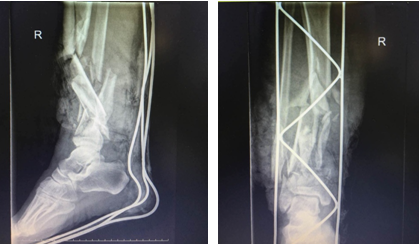

患者右小腿创伤部位CT照片

清创、骨折部位固定